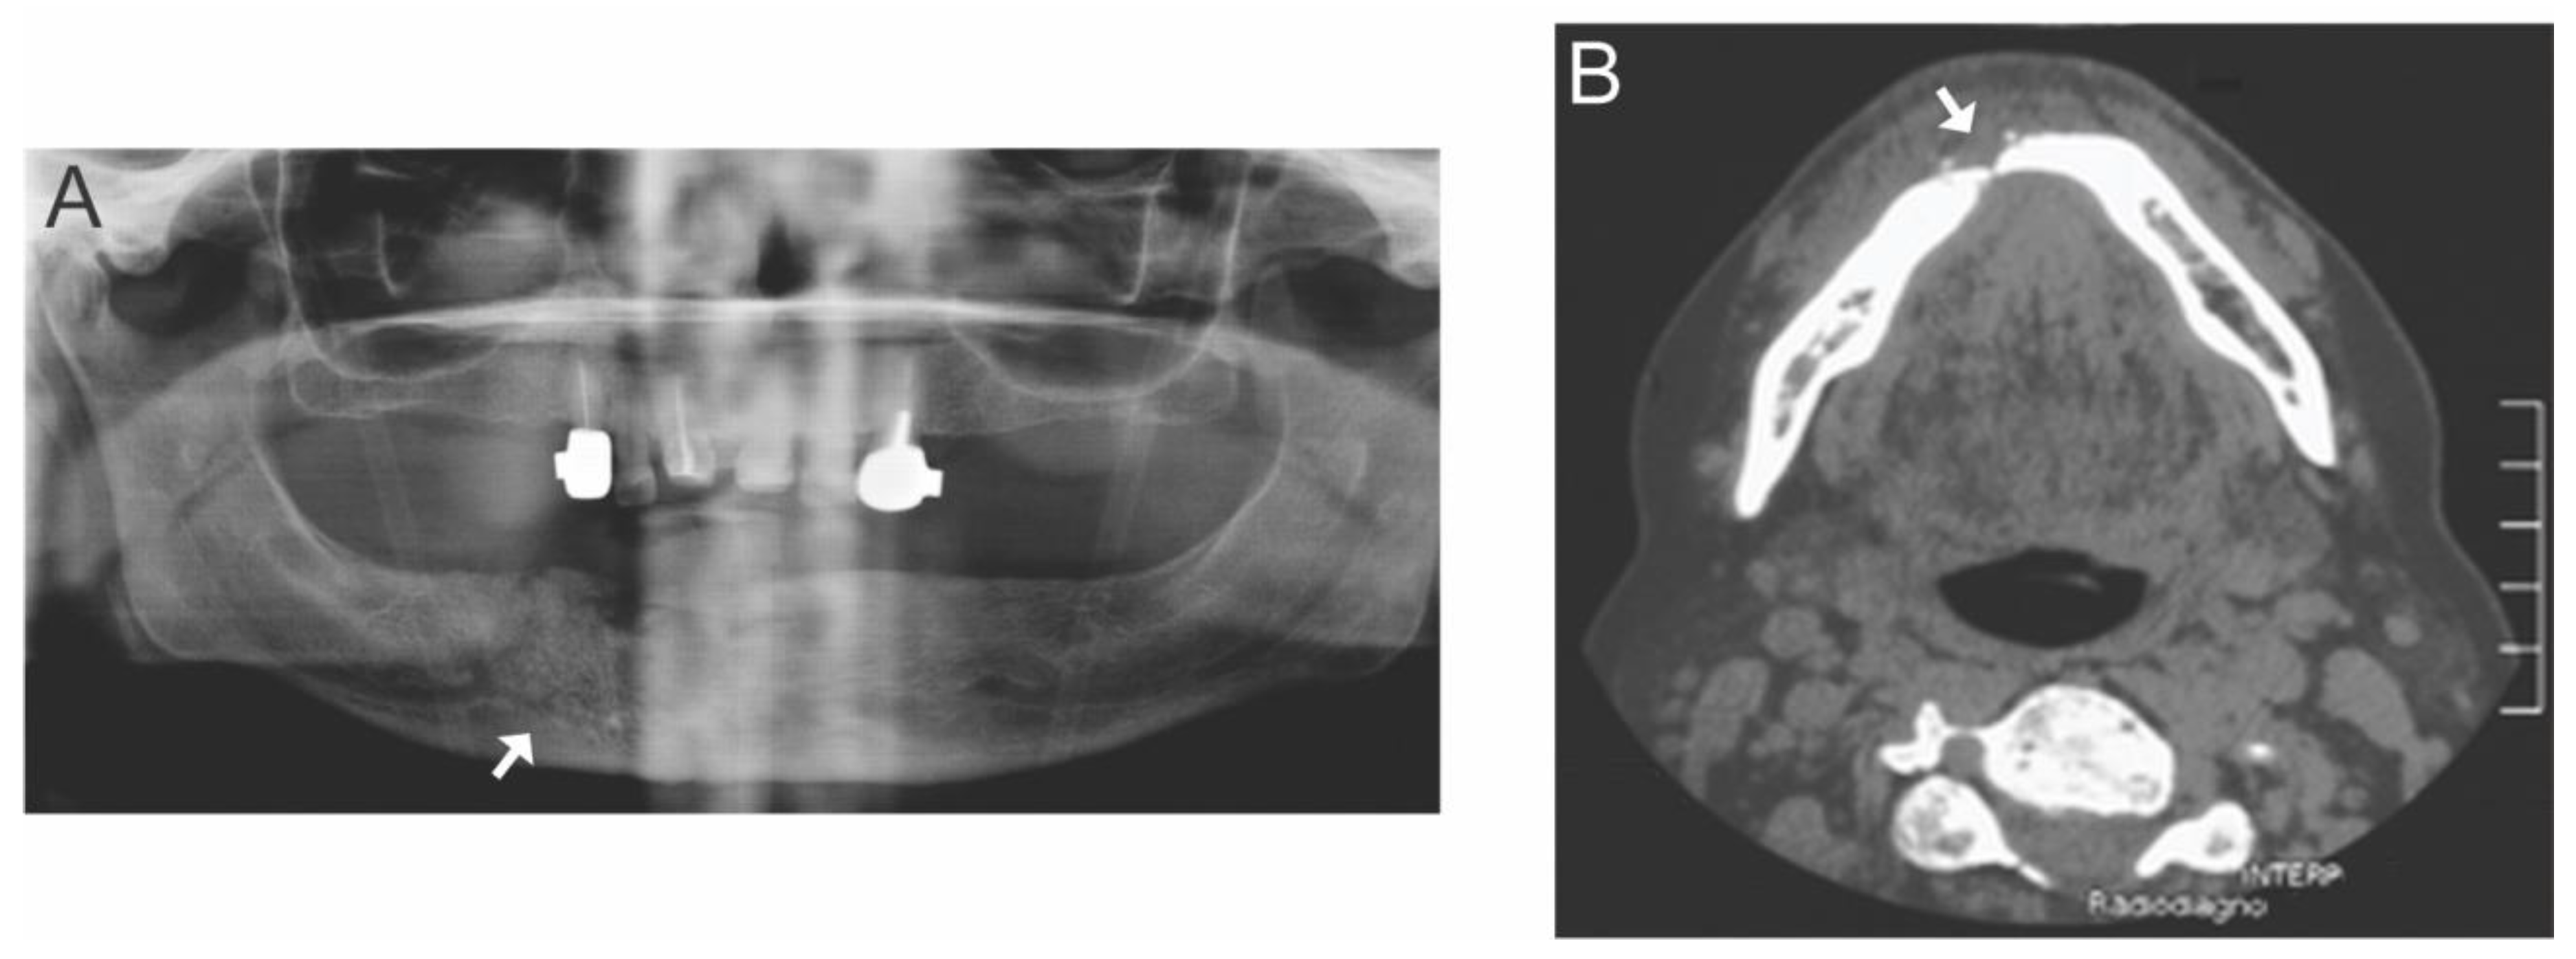

- Miyamoto, I.; Tanaka, R.; Kogi, S.; Yamaya, G.; Kawai, T.; Ohashi, Y.; Takahashi, N.; Izumisawa, M.; Yamada, H. Clinical Diagnostic Imaging Study of Osteoradionecrosis of the Jaw: A Retrospective Study. J. Clin. Med. 2021, 10, 4704. [Google Scholar] [CrossRef] [PubMed]